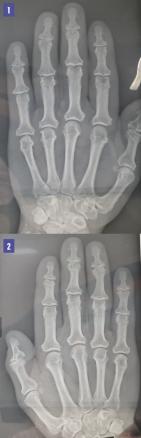

Une femme de 55 ans consulte pour des polyarthralgies périphériques des mains et des pieds d’allure mécanique apparues depuis plusieurs mois. L’examen note une hypertrophie des parties molles, des doigts boudinés, une diminution de la mobilité articulaire des mains et un syndrome dysmorphique crânio-facial non constaté par la patiente (asymétrie légère de la face, base du nez large et épaississement des lèvres). La radiographie des mains montre une hypertrophie de la houppe des phalangettes, la base des phalanges est élargie, avec des ostéophytes réalisant un aspect en ancre de marine des houppes phalangiennes (fig. 1 et 2 ).

À l’examen radiologique, les niveaux de GH (growth hormone ou hormone somatotrope ou hormone de croissance) et d’IGF-1 induisent initialement une hypertrophie du cartilage et des tissus mous, qui est documentée comme un élargissement de l’espace articulaire. À mesure que la maladie évolue, se développe un rétrécissement des espaces articulaires associé à une ostéosclérose et à une ostéophytose avec, exceptionnellement, une hypertrophie des houppes phalangiennes en ancre de marine.2, 3